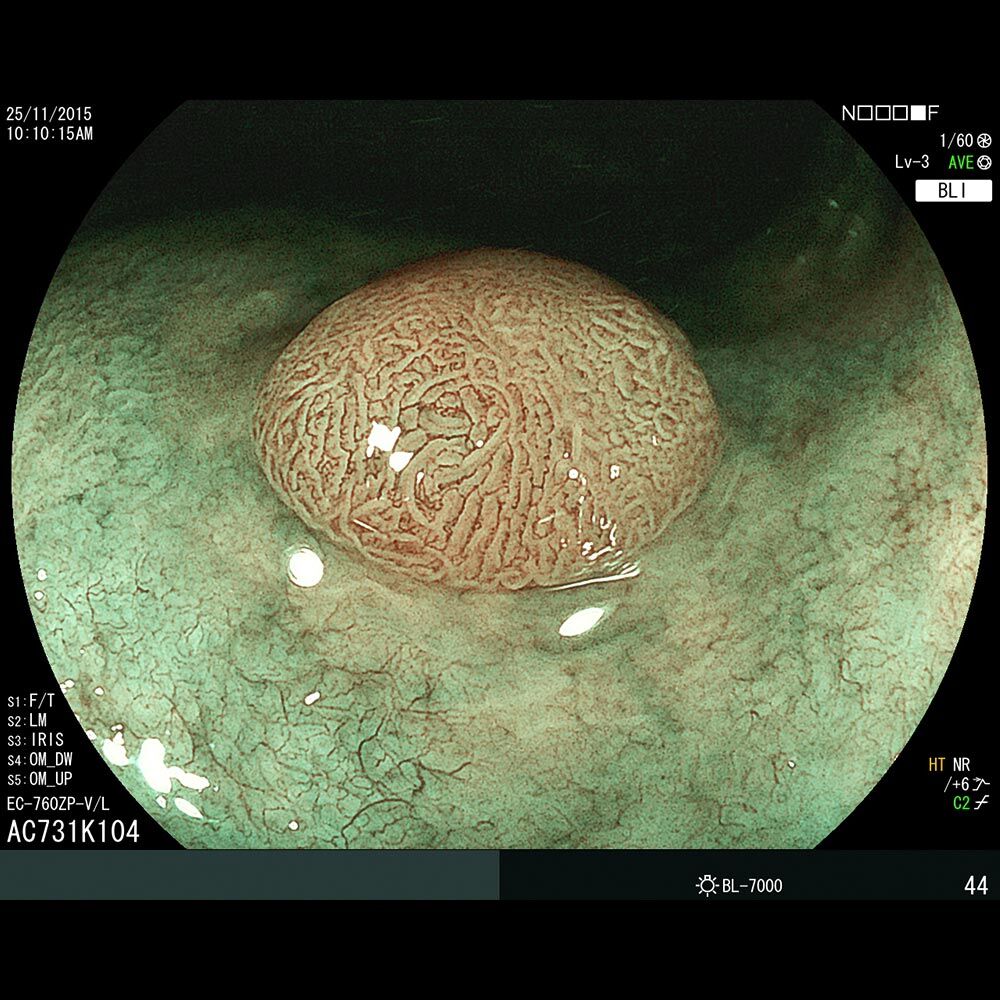

Die Darmspiegelung hilft, dass Darmkrebs gar nicht erst entstehen kann. Denn während der Untersuchung werden auch Polypen entfernt, aus denen sich der Darmkrebs in der Regel entwickelt. Von allen Maßnahmen zur Früherkennung dieser Polypen besitzt die Koloskopie die höchste Empfindlichkeit. Sie weist kleinste Polypen, aber auch Darmkrebs nach, der noch keinerlei Symptome macht. Die Abtragung dieser Polypen erfolgt direkt, wenn sie entdeckt werden. Das geschieht völlig schmerzfrei. Durch die Abtragung der Polypen kann die Entstehung von Darmkrebs effektiv verhindert und die krebsbedingte Sterblichkeit gesenkt werden.